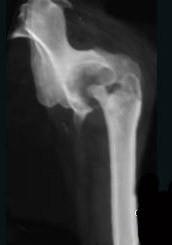

女,27岁,双侧髋部疼痛,肿胀2个月余,继往有髋部外伤史,请结合影像学检查,选出最可能的诊断 ( )A、慢性骨脓肿B、骨结核C、股骨头骨折...